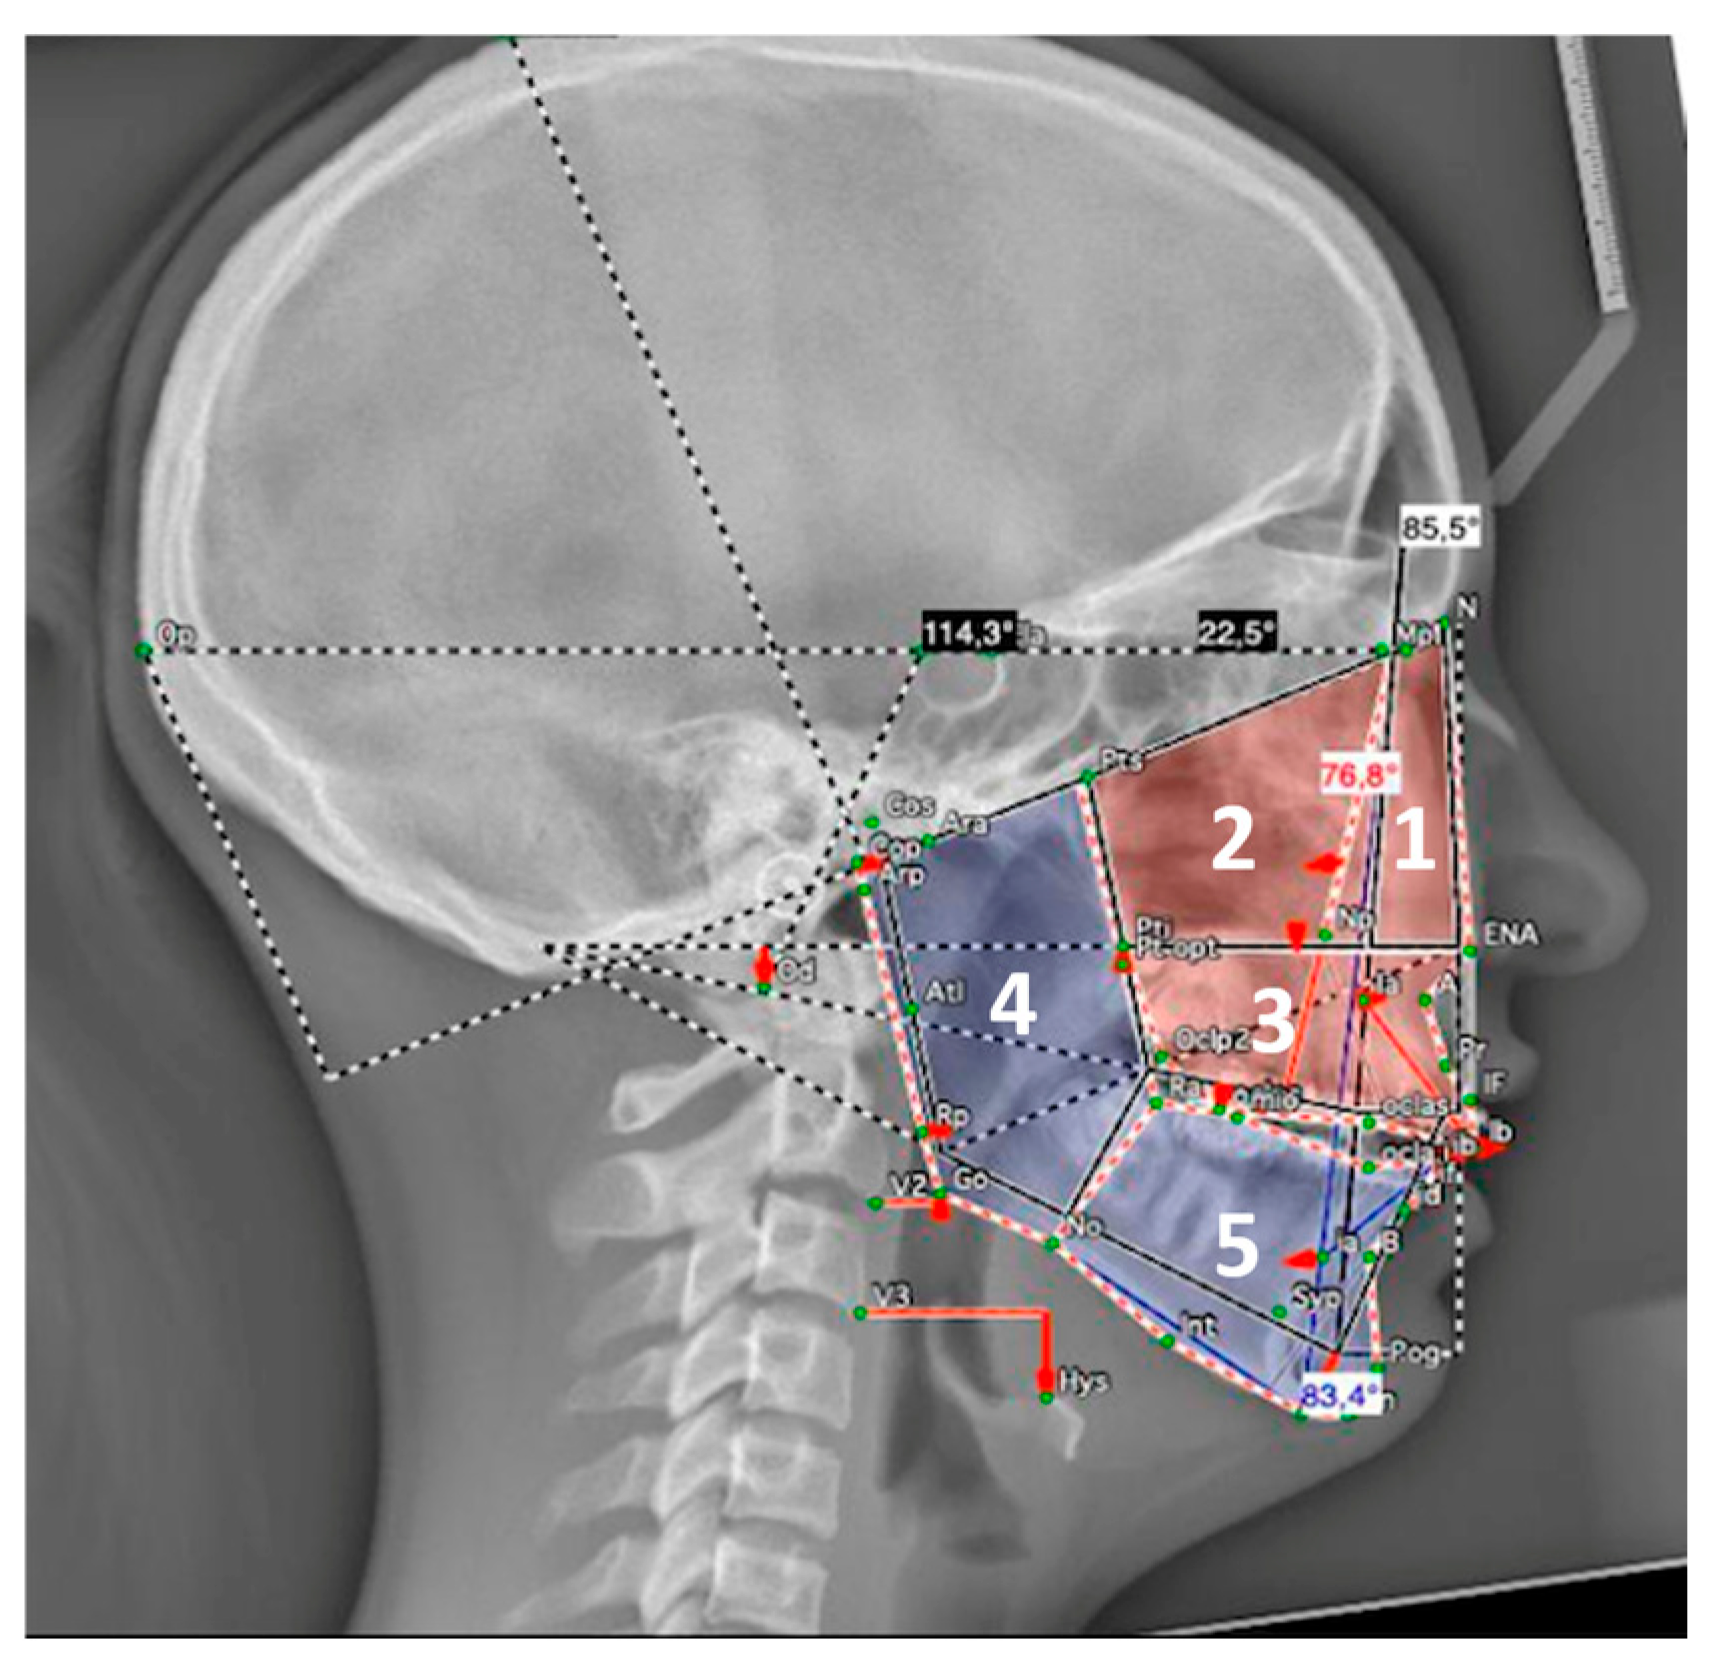

For the architectural analysis according to Delaire, only cephalometric radiographs with a scale were used. Topographic analysis compared the areas of the five distinctive architectural territories of the facial skull (nasopremaxillary, maxillary, maxillary alveolar, ramus, and corpus of the mandible) to patient-specific optimal areas (patient-specific ideal norms). These territories are anatomically defined by four cranial lines (C1-C4) and eight craniofacial lines (CF1-CF8) [36,37] (Figure 3).

3.3.3. Skeletal Cephalometric Analysis According to Delaire (Table 3)

The areas of the nasopremaxillary territory of patients exhibited an increase in area as compared to their patient-specific ideal norms. However, this increase occurred along with a substantial decrease in size of the maxillary territory. Taken together, the sum of these two differences was negative (−75,965 mm2). Nevertheless, the most significant deficit was in the maxillary alveolar territory. Therefore, the global maxillary surface area was less than the norm. Regarding the mandible, an increase in the area of the ramus was observed, along with a decrease in the area of the mandibular body. However, these differences did not reach statistical significance (p > 0.05).